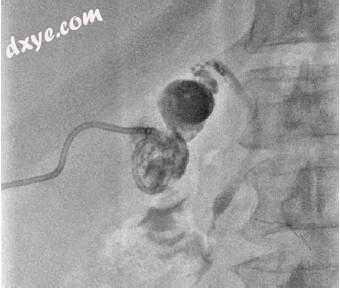

胆结石摘除术在手术室进行。 将经皮管道扩张至16 French,以放置用于内窥镜插入的鞘管(图15.9)。 在直接的内窥镜检查下,用圈套器切除了多个结石,计数为52个(图15.10、15.11和15.12,视频15.2)。 泌尿科服务可协助较大结石的激光碎裂。

ERCP括约肌切开术和肠胃球囊清除术在4天后进行,以评估在器械检测过程中可能已迁移到CBD中的任何结石(图15.13)。

13.jpg

图15.13清除胆囊管和胆总管的球囊,将球囊推到坚硬的导丝上。注意与0.035英寸工作线相邻的0.018英寸安全线之间的直径差